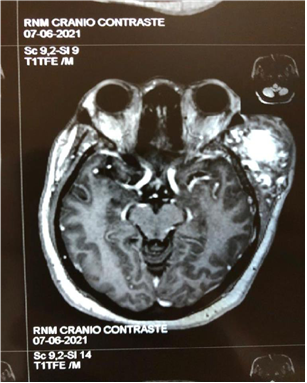

Figure 2A Contrast-enhanced magnetic resonance imaging showing a tumor in the extraaxial region of left frontal involvement.

Figure 2B Contrast-enhanced magnetic resonance image showing a tumor in the extraaxial region of left frontal involvement.

Patient arrived at the service of the Cacoal Regional Emergency and Emergency Hospital (HEURO) with hospitalization on 07/07/2021, 50 years old, female, black, with a previous history of controlled systemic arterial hypertension and reports a tumor in the left frontal region for about 3 years, visible and with an expansive mass. In view of this, a previous biopsy of oncotic aspiration cytology compatible with a benign follicular nodule (Category II-BETHESDA) was requested, where smears showing moderate cellularity were found at the expense of isolated follicular cells, sometimes aggregated amidst histiocytes, lymphocytes and neutrophils, on an amorphous background with a proteinaceous appearance, in addition to abundant colloid and numerous erythrocytes. The immunohistochemical examination showed the diagnosis of epithelial neoplasia of follicular origin and the anatomopathological analysis in the microscopy part showed the presence of an expansive lesion in the left frontal region suggestive of primary epithelial neoplasia with findings of irregular nuclei with clear areas and lumens filled with amorphous material eosinophilic. The macroscopic analysis showed 3 irregular brownish elastic fragments with dimensions of 0.5 cm x 0.3 cm x 1 cm. After performing magnetic resonance imaging, a left frontal extraaxial lesion with bone destruction was evidenced and the patient was immediately referred to a place in a reference service.

Epithelial neoplasms arise from the so-called follicular cells that have their development associated with the influence of thyroid hormones in the tissues.4 In this case report, the appearance of an expansive and compressive tumor in the extra axial region of the left forehead is observed in a female patient. A 50-year-old patient in category II of the Bethesda classification, widely used to evaluate the aspiration cytological results, found a benign nodular pattern of follicular cells in that atypical area, being indicative of an epithelial neoplasm. Therefore, it reflects on the influence of thyroid hormones that generally affect women eight times more often than men.1 With advancing age, many endocrine systems show a gradual change in production, metabolism, action and plasma concentration of hormones, therefore, it is observed that the serum levels of T3 and T4 are reduced and normal or slightly increased levels of TSH and, therefore, an increase in the prevalence of thyroid disorders among geriatric patients is observed, reaching around 2 .0% to 4.0%, while in the general population the prevalence is 0.5% to 1.0%.5,6 Around the age of 50, women experience hormonal changes with hypoestrogenemia and serum levels of follicle stimulating hormone (FSH) that directly impact the follicular cells contributing to the appearance of epithelial neoplasms.7 After the resonance, another aspect of relevance and concern in the case was evidenced, the fact that there is bone destruction in the region affected by the tumor and the patient is urgently referred to a reference unit (Figure 1A - Figure 6B).